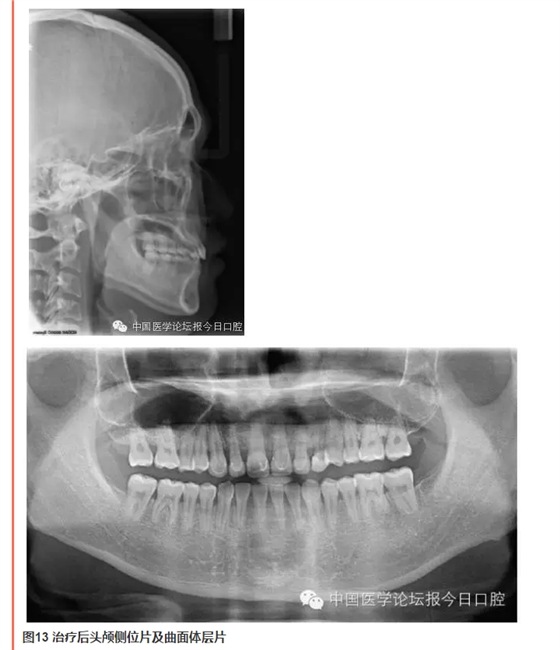

QQ圖片20150714135555.png

QQ圖片20150714135614.png